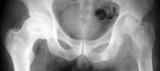

Положили в больницу, месяц лечился антибиотиками. После выписки боли сохранялись. В декабре 2005г. направлен на эндопротезирование в Новосибирск. В дороге появилась гиперемия сустава. В Новосибирске выявлен остеомиелит головки, гнойный коксит. Выполнена резекция головки. Проведено лечение коксита. Сустав вскрывался из трех доступов: задний, латеральный и паховый. Состояние улучшилось. На всех послеоперационных рубцах сформировались свищи с гнойным отделяемым. В настоящее время локальный статус прежний. Ходит на костылях, не наступая на ногу. 10 апреля направил на КТ. Заключение: отсутствуют головка и шейка бедренной кости - состояние после резекции. Бедро в состоянии подвывиха. Очагов деструкции не выявлено. Плотность костной ткани в крыше вертлужной впадины 483 ед.Н, дно - 197 ед.Н, в верхней 1/3 бедренной кости, ниже малого вертела, 95 - 167ед Н. Вопросы: объем санирующей операции? сроки эндопротезирования? -- Юрий Алексеевич Булахтин, главный травматолог Камчатского Военно-морского госпиталя

Да как тут скажешь, кроме как "достаточный"? По этим мелким рентгенограммам мало что понятно. Надо то есть сделать радикальную обработку, ввести в свищи краску, открыть сустав, все окрашенное и